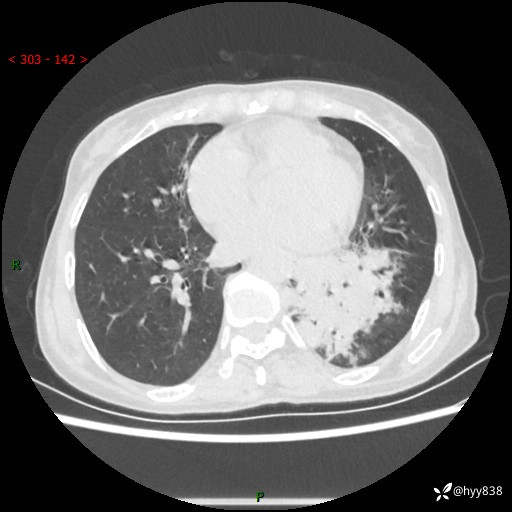

胸部CT平扫+增强